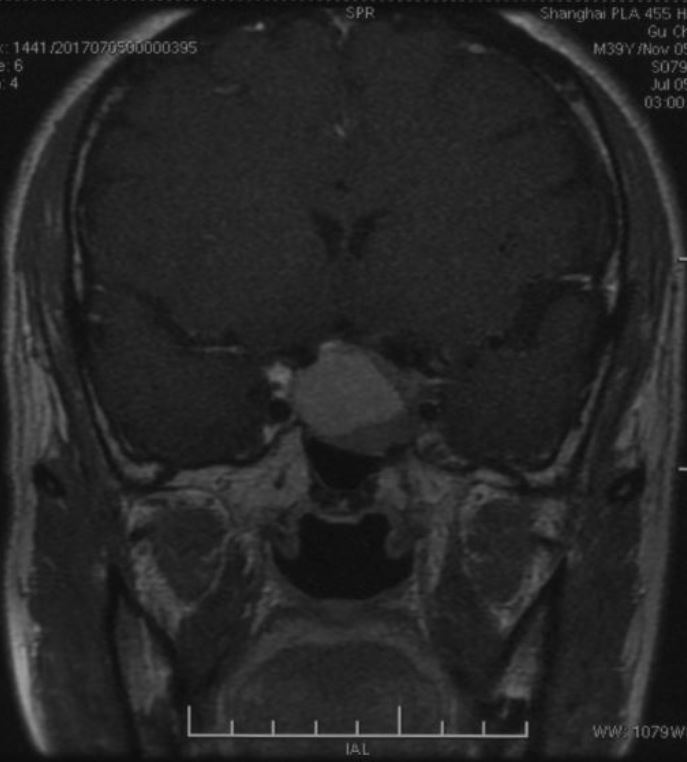

鞍区磁共振检查发现:鞍区肿瘤卒中可能,肿瘤侵犯双侧海绵窦、颈内动脉,鞍隔被顶起,鞍底部分塌陷。复旦大学附属肿瘤医院神经外科高阳

冠状位增强